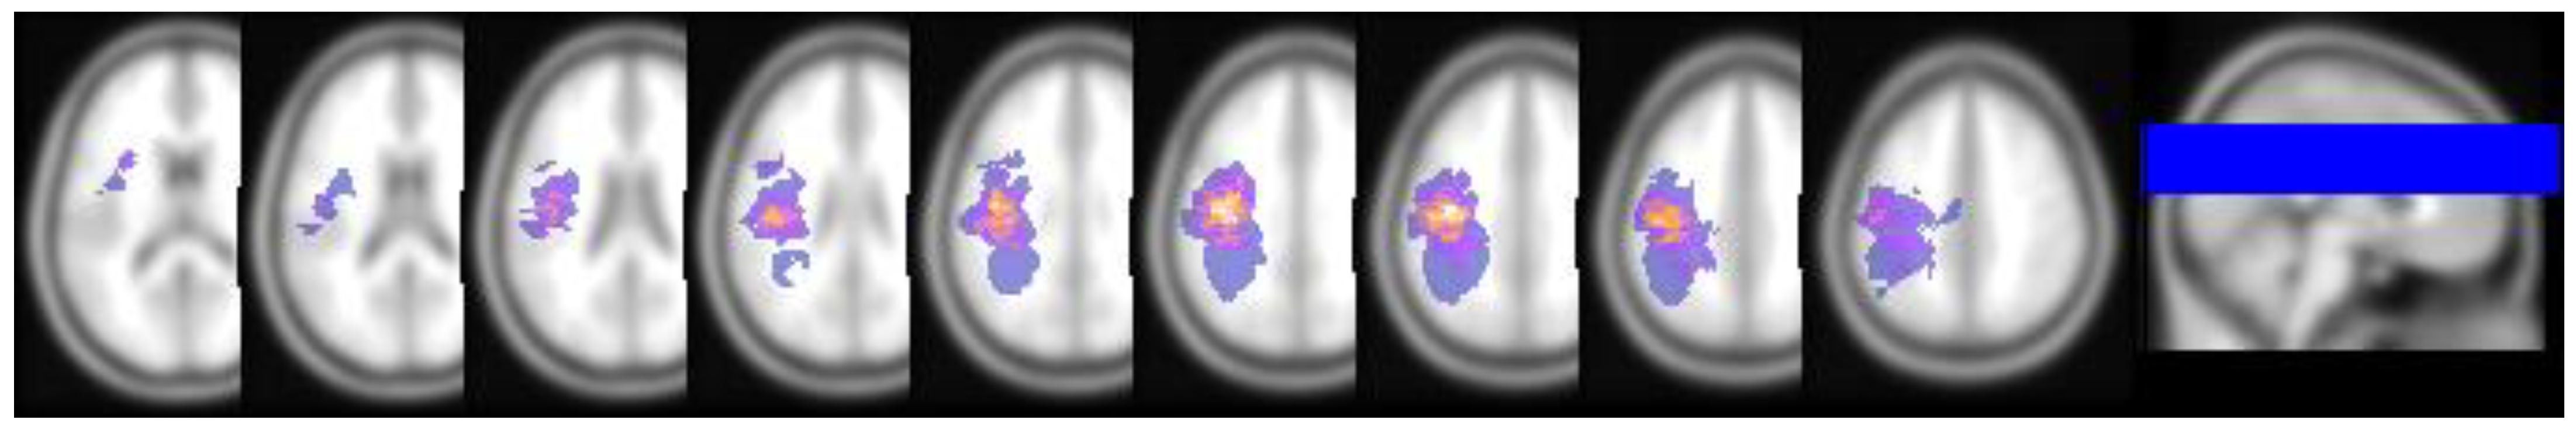

3.4. Nodal Properties Differences